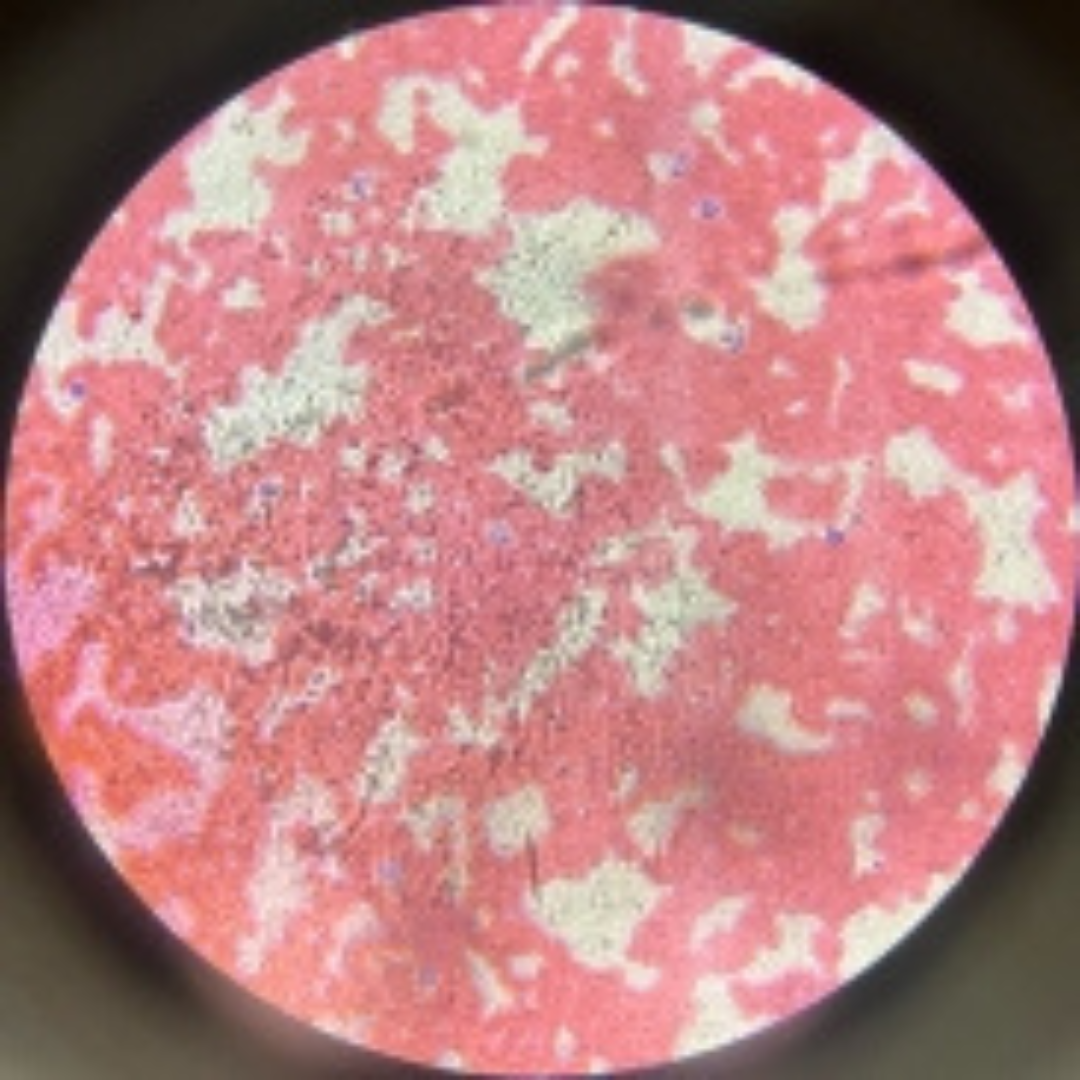

Bone Marrow

Bone Marrow